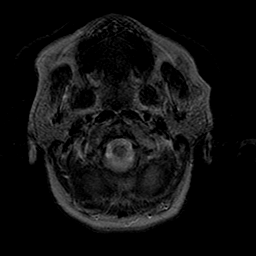

Stroke:T2-weighted MR #1 -- Slice #0

[Home][Help][Clinical] Slice 0